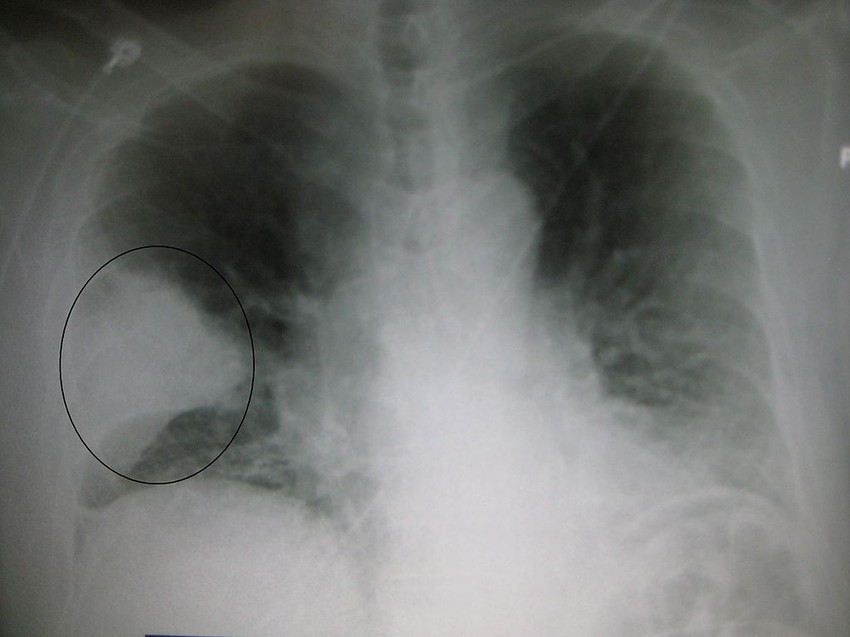

Így néz ki röntgenfelvételen a koronavírusos tüdőgyulladás:

Koronavírus okozta tüdőgyulladás röntgenfelvétele (a fehér rész az érintett) Forrás: https://www.journalpulmonology.org/

Jól körülhatárolt tüdőgyulladásos (jobb középső lebenyi) terület röntgenképe